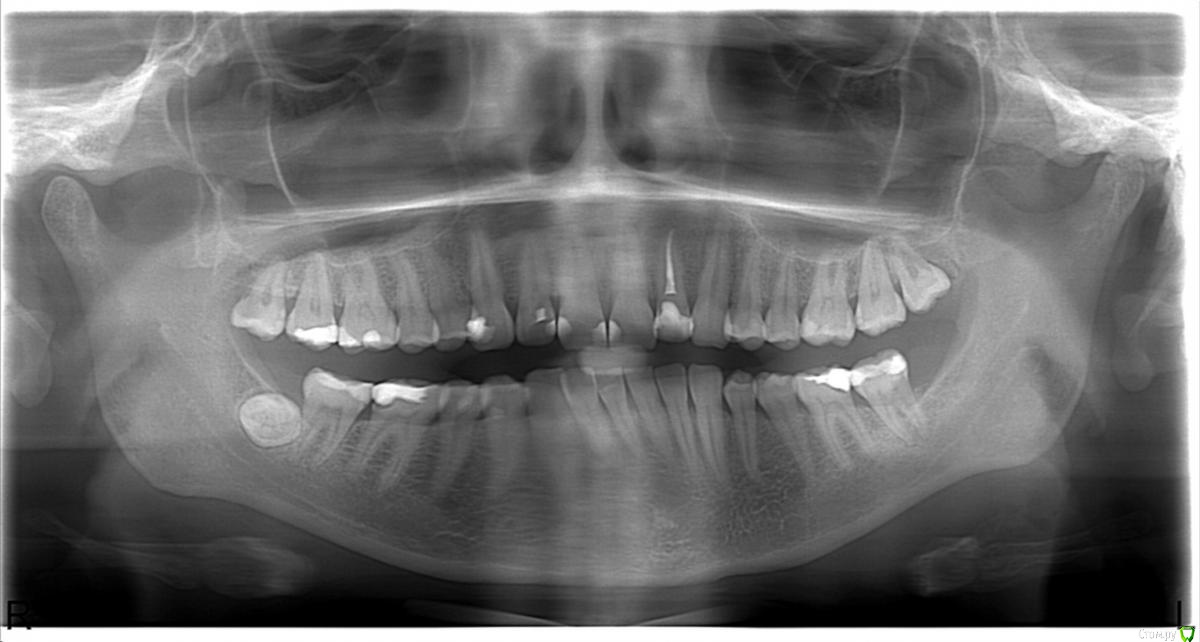

Galyana Опубликовано 13 июля, 2015 Автор Поделиться Опубликовано 13 июля, 2015 снимки,фото выкладывайте.Вообще я обратилась к врачу, так как у меня ныла верхняя челюсть, но я не могла определить какой конкретно зуб болит. Врач сказала, что ноет из- за тройки и вылечила ее. Но еще сказала, что надо удалять восьмерку. Вот думаю удалять или нет. Но челюсть все равно периодически ноет. Может и не надо было депульпировать тройку, явно она меня не беспокоила. Но это все размышления, а вот снимок до депульпации тройки Ссылка на комментарий

anvladd Опубликовано 13 июля, 2015 Поделиться Опубликовано 13 июля, 2015 По поводу 3ки,все зависит насколько сильно разрушен зуб,если судить по этому снимку,то я бы коронку не ставил,хотя бог знает как доктор расскрывала,сколько тканей осталось.Вы написали,что боли остались,надо бы посмотреть 17,16,12,11 зубы и 47,46. Все 8ки я бы удалил. Ссылка на комментарий